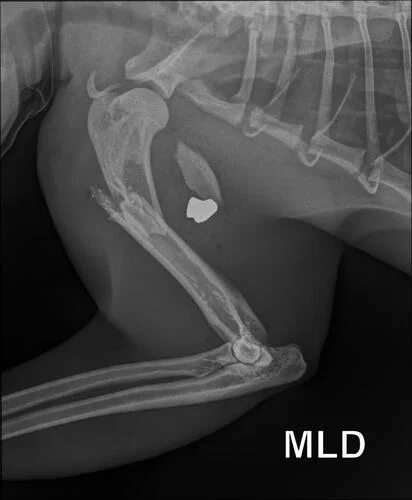

O gato Mimo, um dócil “laranjinha”, foi vítima de violência animal ao ser baleado pela segunda vez, sofrendo ferimentos graves que agora exigem uma cirurgia complexa para evitar a perda de um membro.O gato foi baleado em Cascavel, no Oeste do Paraná.

O exame de raio-x revelou que o ferimento não era uma queda, mas o gato foi baleado com projétil de arma de fogo. Alguém teria atirado no animal de forma intencional.

Mimo segue internado para estabilização e aguarda o procedimento cirúrgico para tentar recuperar o membro atingido.